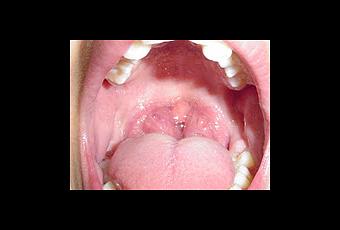

- La frecuencia de los episodios de anginas es de al menos siete episodios en el último año, al menos 5 episodios por año durante 2 años o al menos 3 episodios por año durante 3 años. Estos episodios han de ser anginas “verdaderas”: dolor de garganta, temperatura> 38,3 ° C, adenopatías cervicales (ganglios) y exudado amigdalar (pus) o un test positivo para estreptococo del grupo A beta-hemolítico

- El niño tiene infecciones repetidas con amígdalas hipertróficas que pueden afectar a su sueño, su crecimiento o a su rendimiento escolar. Otra indicación es la hipertrofia amigdalar, sin infecciones, que interfiere el sueño tranquilo (ronquidos, apneas, cambios de posición frecuentes) que se puede demostrar con un estudio del sueño (polisomnografía) si es necesario